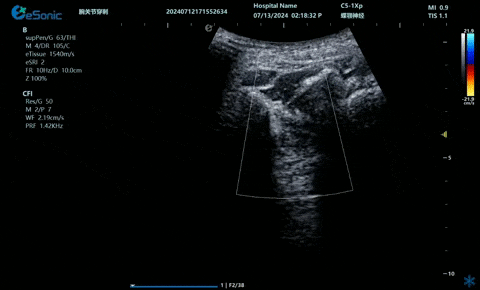

超声引导下蝶颚神经节阻滞术

大雁征-上颌动脉切面